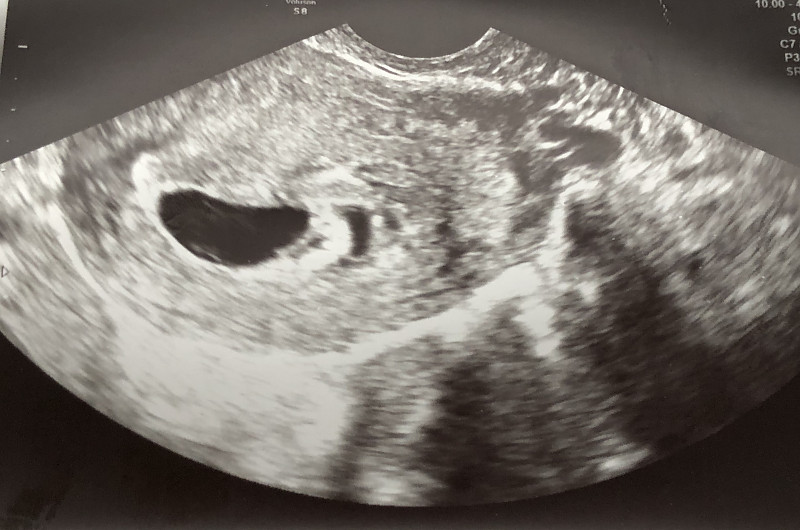

Galiu parodyti nuotraukytę, kurioje gydytoja nieko nemato ir sako, kad yra atsisluoksniavimas bei mato hematomą.

Mano atrodo taip...bet aš nelabai ir suprantu...

Panašiai atrodė pas mane, kai pagal mm buvo 7sav+2d, Tik kitokia forma buvo.

Dar vilties tikrai Jums yra, kad gali pasirodyti mažylis..